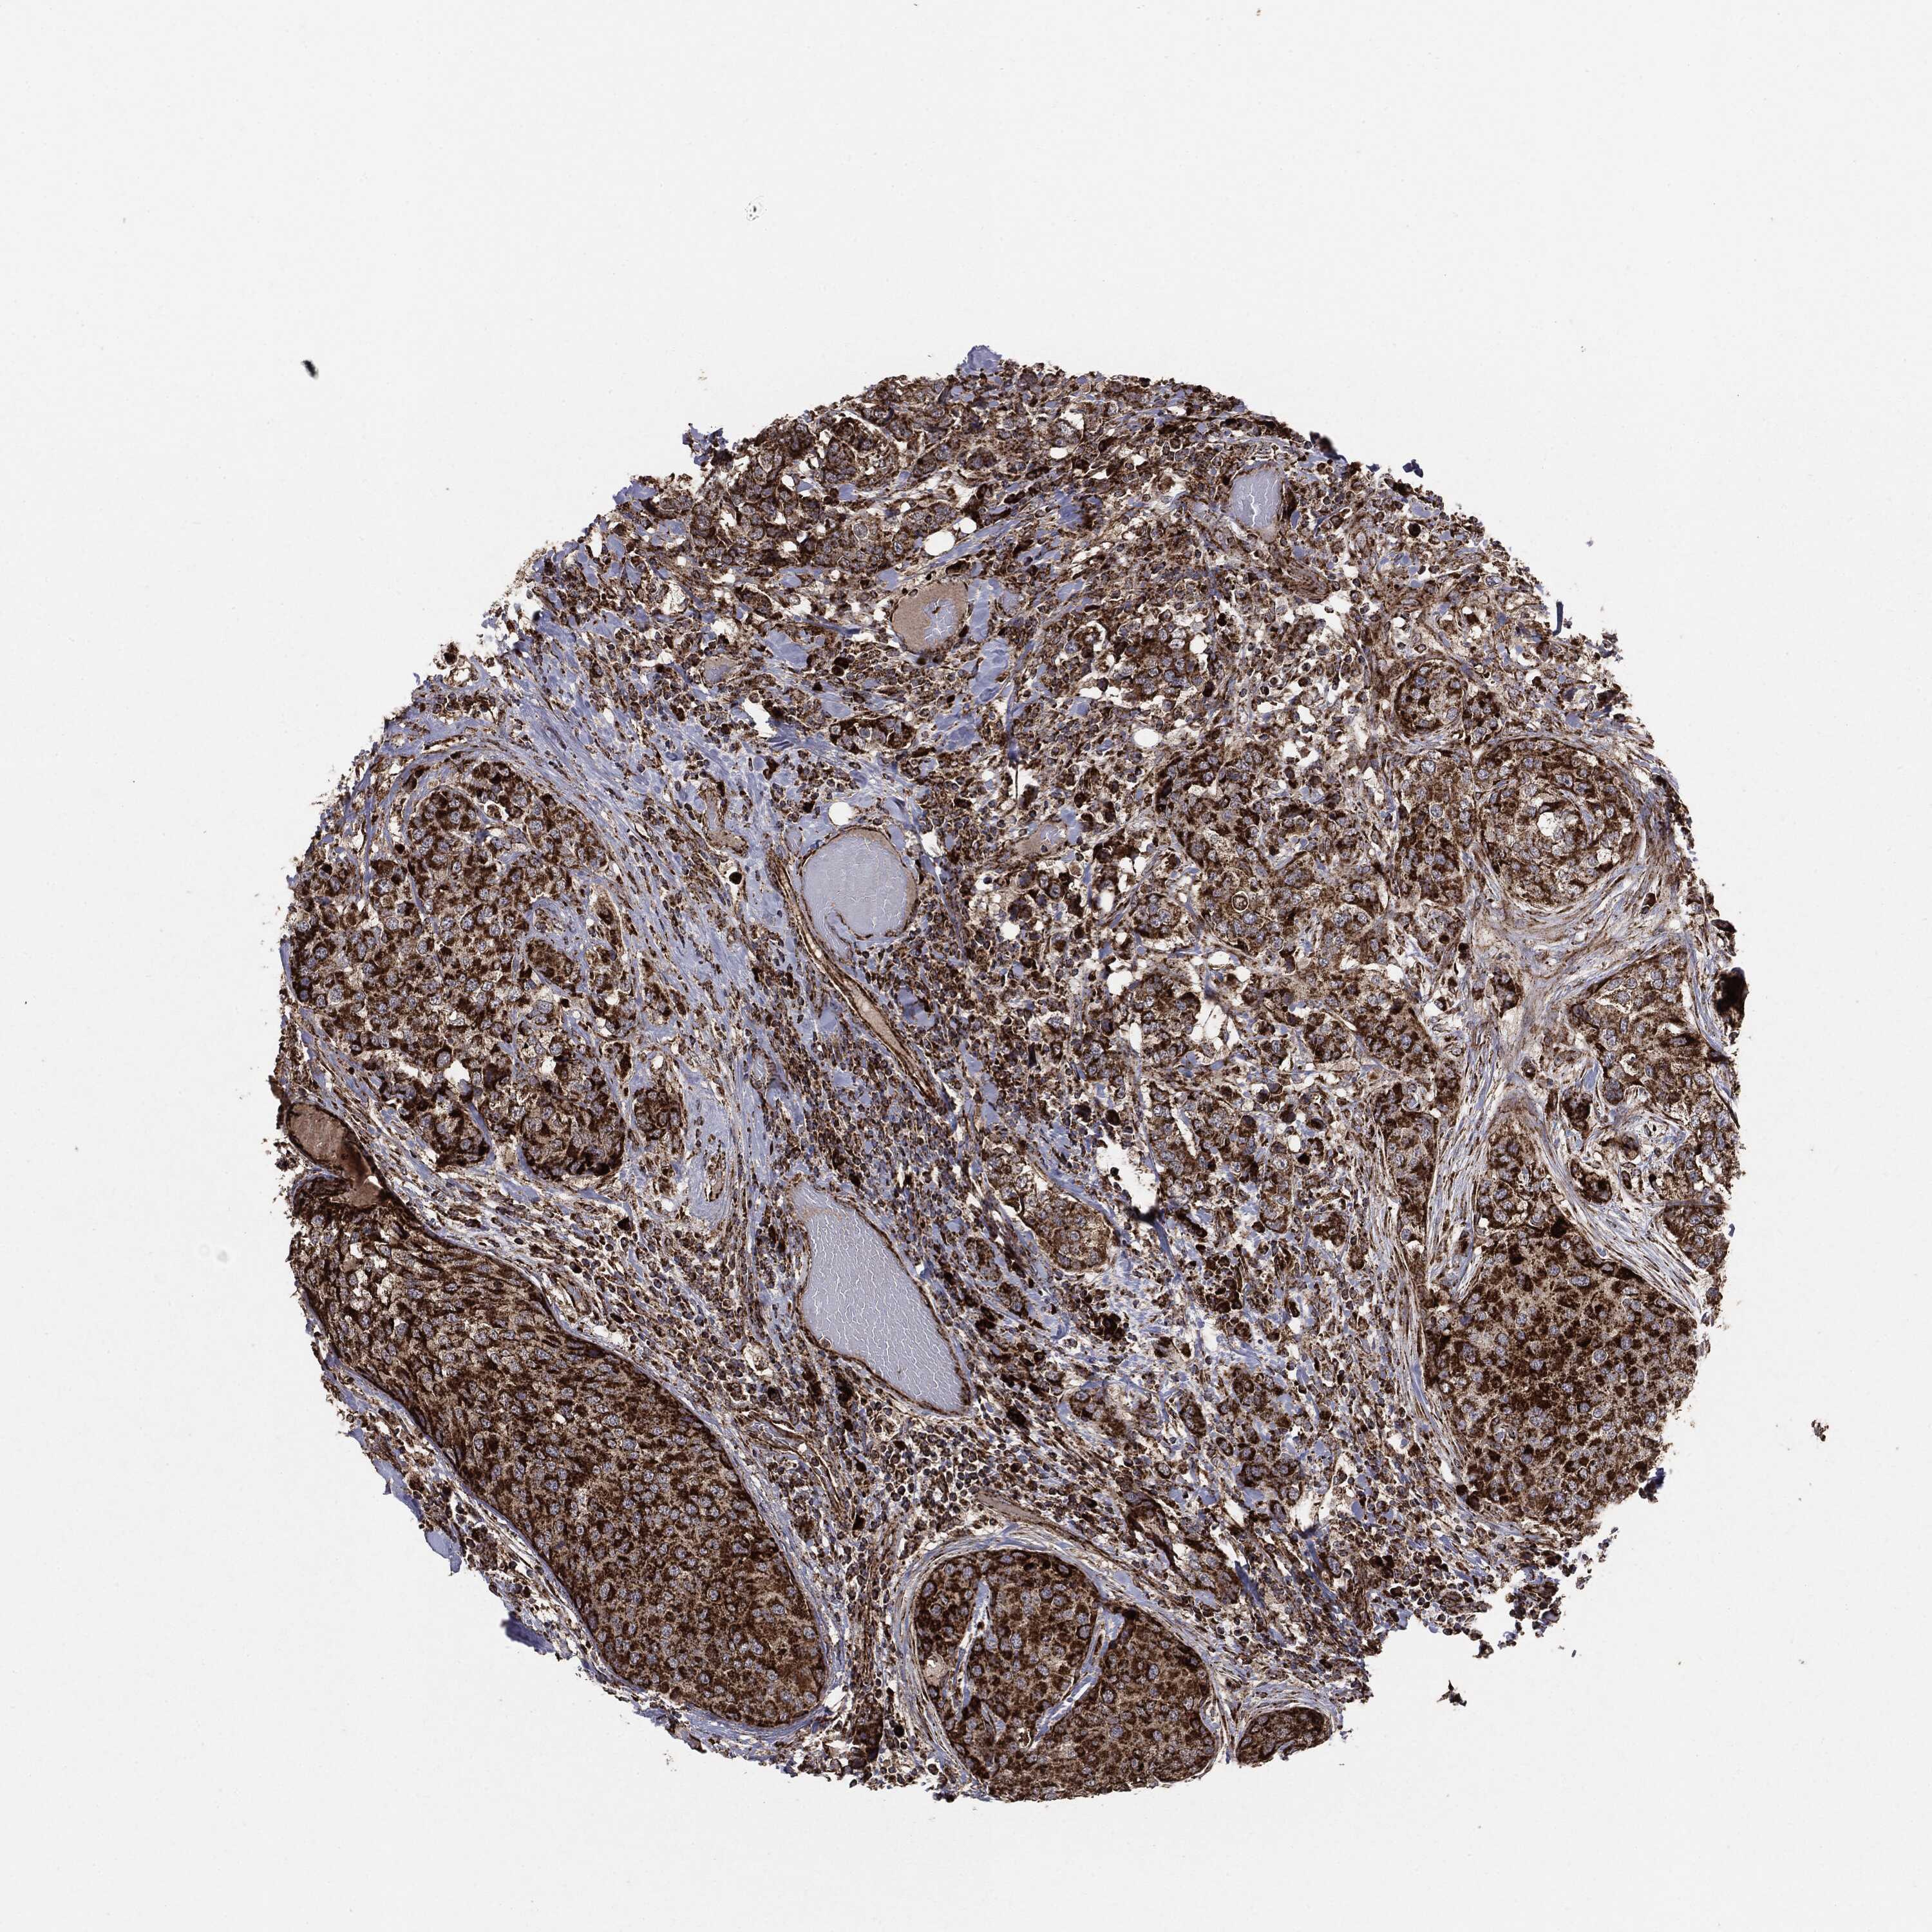

CANCER BREAST CANCER Show tissue menu

BRCA TCGA BRCA VALIDATION PROTEIN EXPRESSION